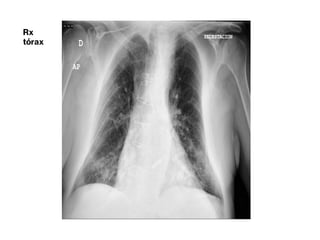

Rx

tórax

PRUEBAS EN URGENCIAS ECG: FAa 100 lpm, BRIHH, déficit de crecimiento de la onda R en precordiales. GSA aa: pH 7.5, pCO2 31, pO2 60, Lact 0.9, Glu 107, K 3.8, Na 134, PAFI 285. Hemocultivos. PCR SARS CoV2